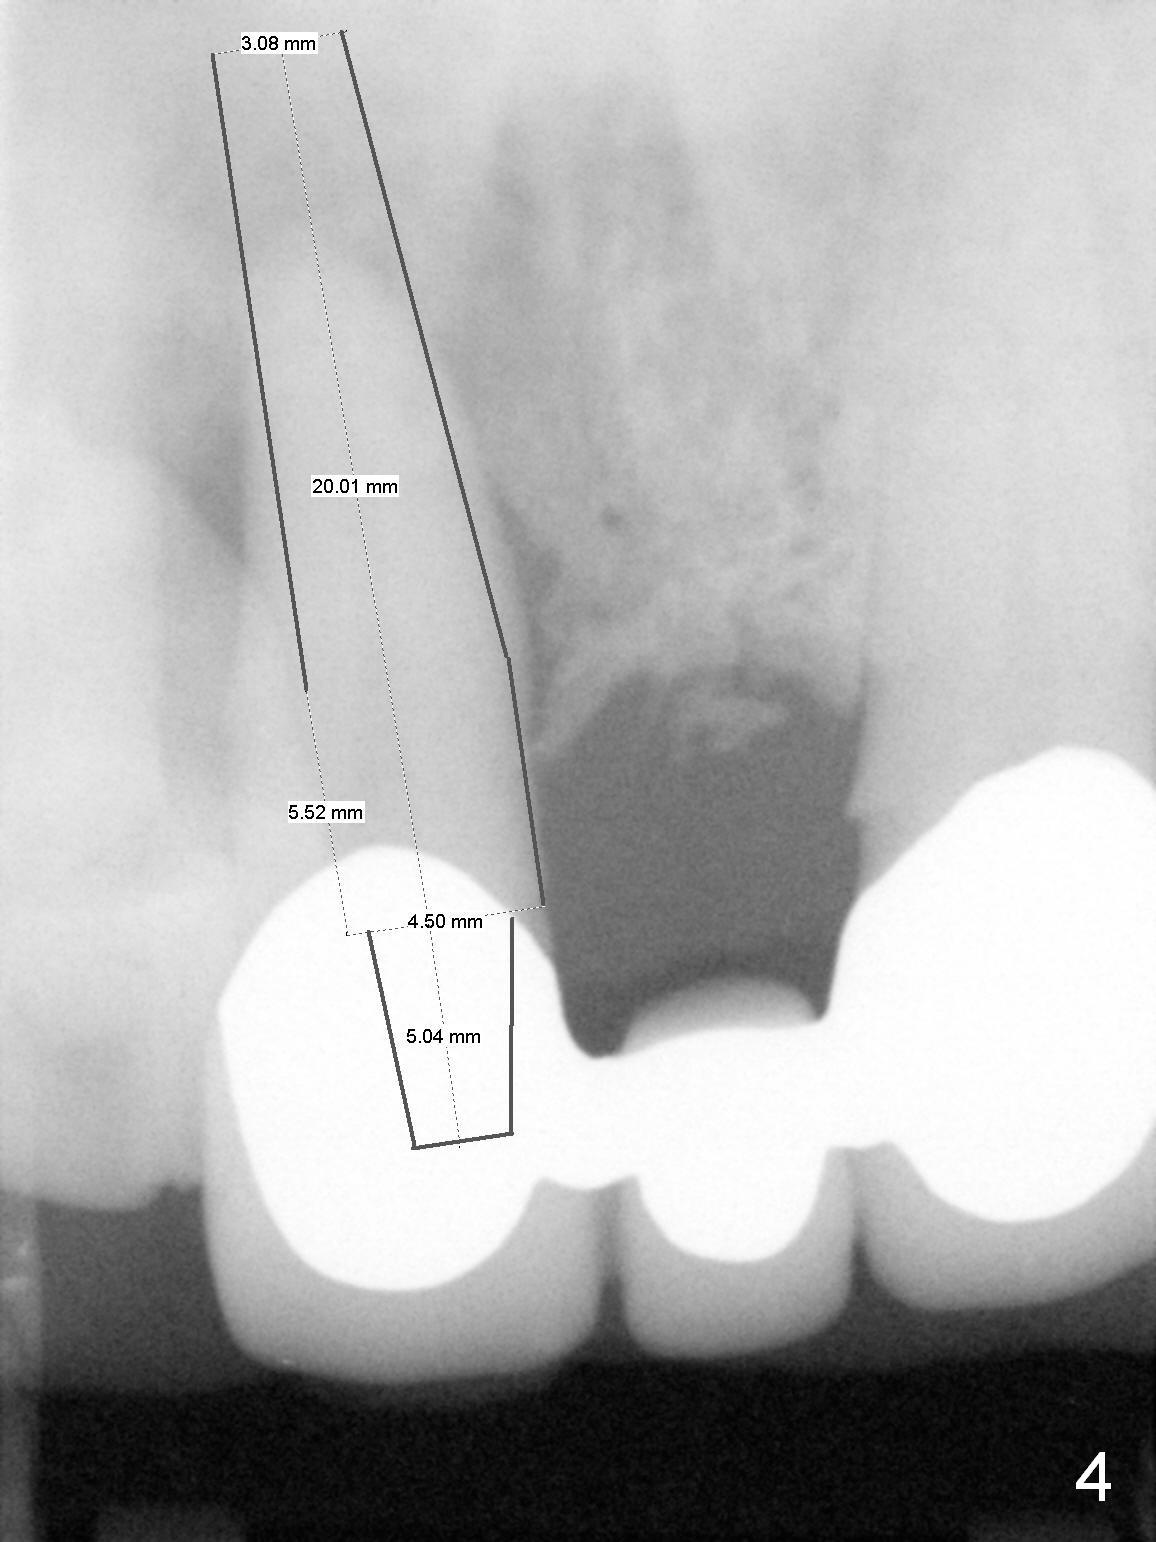

The 74-year-old patient is excited about having 3 implants placed without discomfort (1,2). He wants to take care of a loose FPD spanning from #8 to 9 (Fig.1). It appears that #8 is non-salvageable (Fig.2 * with deep pockets). There is severe bone loss around the affected tooth (Fig.3; Osteotape is expected for buccal and lingual defects). In addition, the Incisive Canal is abnormally large (arrowheads). The coronal end of a 4.5x20 mm implant and a 3.5x5 mm abutment will be slightly deviated mesially (Fig.4), since the 3-unit FPD will be converted to 2 single unit crowns. Surgical guide is ready. The 1st step is to section between #8 and the pontic (Fig.5; green outline: implant; red: abutment). If primary stability is low, the immediate provisional (Fig.8 white area) will be bonded the tooth #7 and the pontic as a supplementary measure (blue areas). Once the implant is osteointegrated, the distal portion of the pontic (Fig.7 *) will be removed. Acrylic is added to the mesial portion of the provisional (Fig.8 *) so that the papilla (P in Fig.7) will be pushed mesially and incisally (Fig.8 arrowheads). The step will be repeated a few weeks later (Fig.9). It could be done bilaterally at the same time by removing #9 crown and converting to the provisional. Finally the pontic will be removed. Two relatively wide crowns will be fabricated if the patient is satisfied with the provisional.